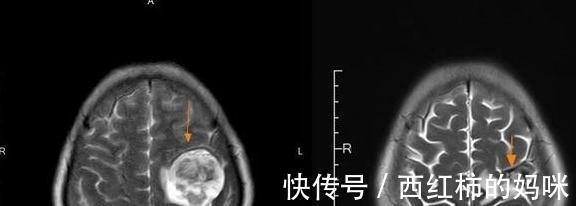

而出院后,病人不但度过了三个月的平均生存期,更是在三年时间的复查里,没有发现病灶的增大以及增多。2018年7月,病人再次因出现头昏、短暂性抽搐和昏迷等症状来到了医院复查。复查结果显示脑内转移瘤出现了增大,医生再一次根据患者的情况进行了对应的化疗和靶向治疗,配合中医药治疗。而后,患者肺部及颅内肿瘤明显缩小,病情稳定,身体情况得到了好转,胸闷头昏,咳嗽咳痰症状基本消失,没有再出现抽搐和昏迷等症状,出院以后,患者继续配合中医药治疗。而上个月,患者又一次来到我们医院进行复查,我们发现病灶比较稳定,没有出现增大的情况。

文章插图

【 晚期|两位肺癌晚期患者,只因做好了“四件事”,生存期明显延长】左:2018年7月治疗前,右:2019年11月

而截止到上个月,这位病人已经距离诊断肺癌晚期伴脑转移过去了5年多。病人也非常开心的给我们分享到:当时听说平均生存期只有三个月了,本来都想放弃治疗了,还好自己积极的治疗尝试,又多活了4年。听着病人喜于言表的分享,我们可以看到她身上的乐观积极,尽管癌细胞仍然在她的身体内,但这并不影响她每天积极乐观的生活,过好当下的每一天。